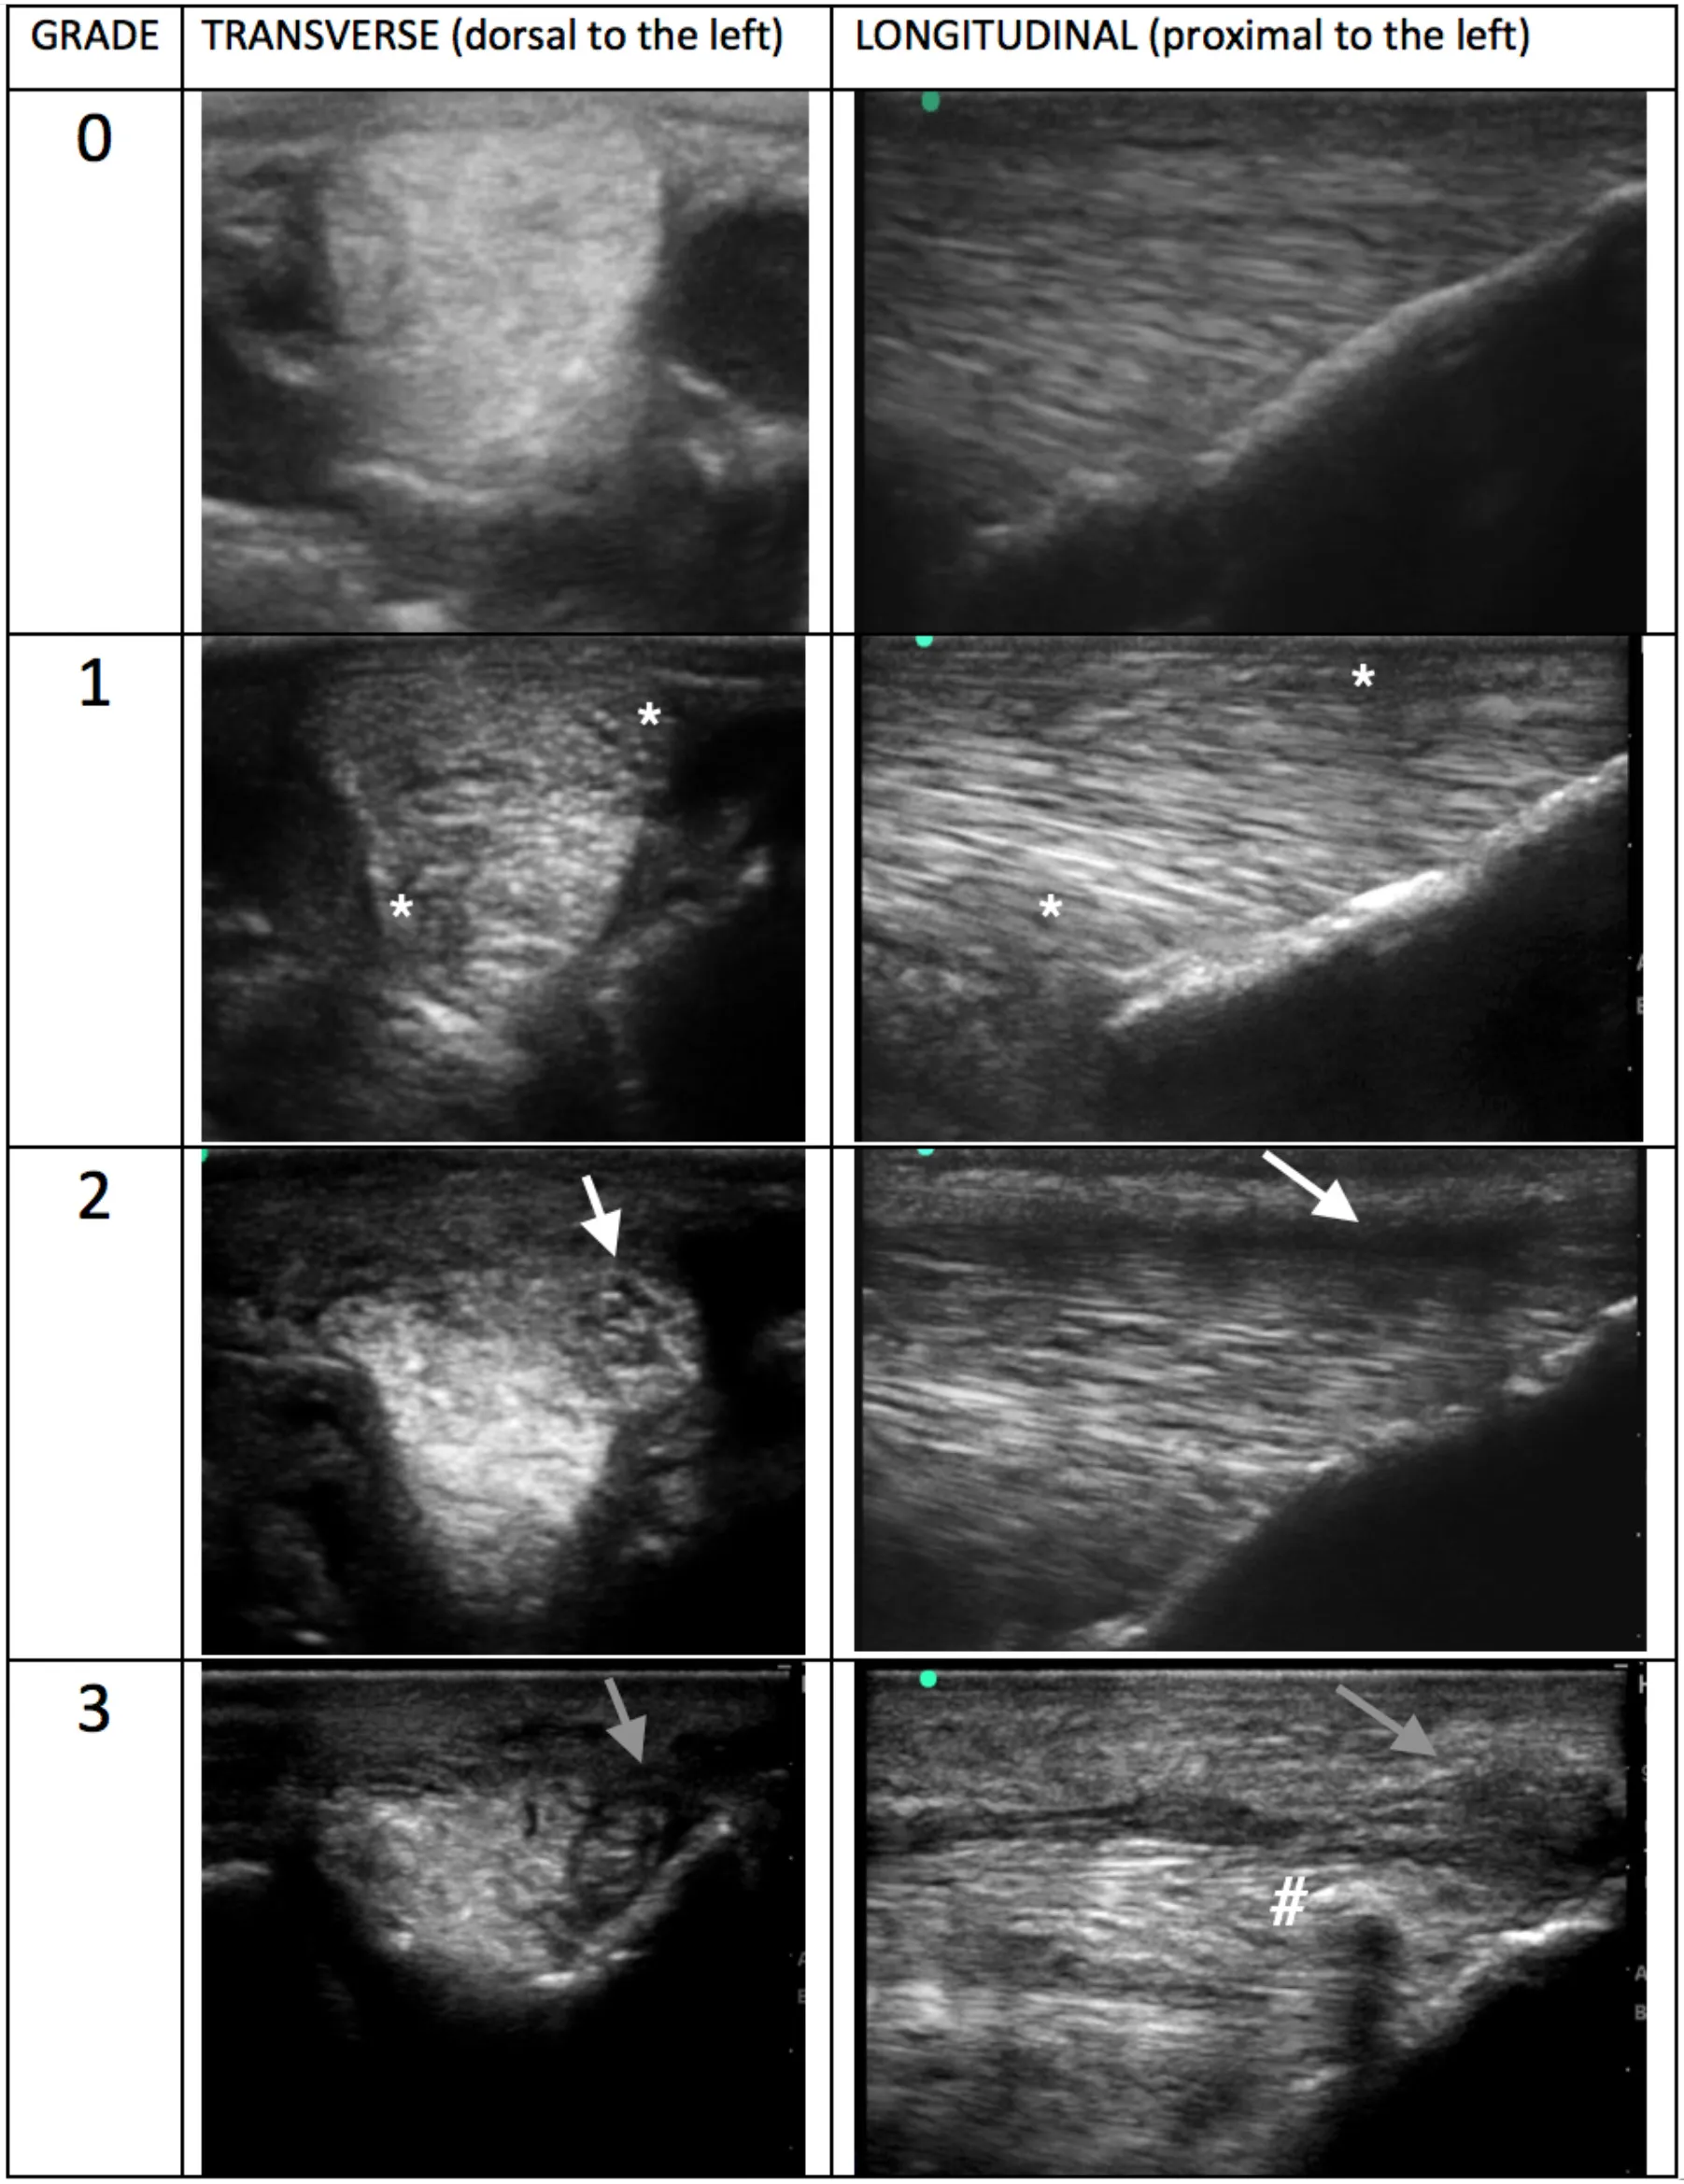

Ultrasound images were reviewed subjectively by two independent experienced clinicians, both of whom are both Diplomates in both the European College of Veterinary Surgery and The American College of Veterinary Sports Medicine and Rehabilitation. They were designated as observers “A” and “B.” Observers were blinded to patient identity, limb and laterality. Images were electronically stored in DICOM format then reviewed on the workstation OsiriX. Detailed description on analysis, grading and example ultrasound images in both transverse and longitudinal planes were provided to each observer prior to the start of evaluation. The ultrasonographic appearance for each image acquired was graded on a previously published 0–3 ordinal scale (8), 0—normal (regular echogenicity and fibre pattern); 1—mild hypoechogenicity, subtle irregular fibrillar pattern; 2—extensive regions of mild hypoechogenicity, regions of moderate heterogeneity, small focal disruptions of fibrillar pattern; 3—regions of marked disruption of fibrillar pattern, large anechoic core defect. Fibre/fibrillar pattern in this case refers to the presence or disruption of long linear parallel echoes on the ultrasonograms. A total of 64 image slices were reviewed per horse, eight static slices were graded for each SLB. For further analysis, an overall “branch grade” was then assigned based on the highest grade given to any image slice on the branch. CSA was measured after image storage using the workstation software OsiriX. All branches were measured using the transverse ultrasonogram at the level of the section one slice proximal to PSB insertion. Measurements were recorded in cm2 to the third decimal place. Presence of periligamentous fibrosis was also recorded by the observers. The increased periligamentar echogenicity was made subjectively and assessed based on clinician experience and previously published data. It was recorded as increased for a branch if any of the eight sections showed an increase, but was not qualified or quantified beyond noting its presence (5).

Combined data showing prevalence of each branch grade is represented in Figure 2, which demonstrates the frequency of grades for each individual observer, as well as where there was agreement. These grades are the overall branch scores, which have been assigned based on the worst grade given to an ultrasonogram slice in that branch. All but one horse had at least one branch that was grade 2. Grades given by observers A and B have been summarised and combined in Table 1: grade 0 0/960 (0%), grade 1 394/960 (41%) and, grade 2 554/960 (58%), and grade 3 12/960 (1%). Examples of each grade from horses in this study are shown in Table 2. The median number of grade 2 branches per horse for observer A was 4/8, and observer B was 5/8. The distribution in grades between forelimb vs. hindlimb SLBs was significantly different for both observers (observer A P = 0.001 and observer B P = 0.002). More grade 2 and 3 abnormalities were recorded in hindlimb SLBs. Combined data showed 255/480 (53%) of forelimbs and 321/480 (67%) of hindlimbs were graded 2 or 3. Comparison was also made for laterality in SLBs graded 2 or 3: 117/240 (48.7%) lateral and 131/240 (54.5%) medial for observer A, vs. 148/240 (61.1%) lateral, and 170/240 (70.8%) medial for observer B. The prevalence of grade 2 or 3 SLBs was higher in medial branches for both observers, but was only statistically significant for observer B (P = 0.026), not for observer A (P > 0.05).

Table 2. Example ultrasonograms in transverse and longitudinal for grade 0–3 branches taken of SLBs from horses included in this study.